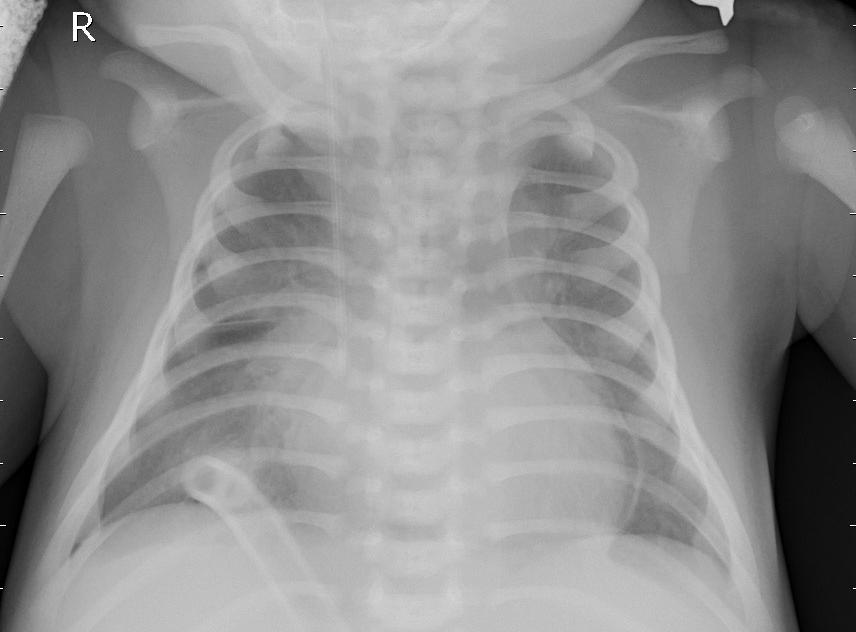

7. Application of RCRI Measure in Image Processing

To ensure the accuracy and reliability of our results, we have taken into account six chest X-ray images from the publicly available chest X-ray 2017 dataset, contributed by kermany2018labeled. These images include samples from healthy individuals and patients diagnosed with pneumonia. For analysis, each X-ray image was converted into a 50×5050\times 50 pixel grid, resulting in 2500 cells per image. The intensity of the gray level of each cell was recorded as a real number ranging from 0 (black) to 1 (white), effectively capturing the grayscale distribution of the image. The α\alpha and β\beta are take as 55.

Using these six images, we generated all 36 possible pairwise combinations. For each pair, we are estimating the Relative Cumulative Residual Information (RCRI), which serves as a measure of discrepancy between the Gray level distributions of the images.

As illustrated in Figure 2, images (a), (b), and (c) correspond to normal chest X-rays, while images (d), (e) and (f) represent pneumonia-infected cases. The calculated RCRI values are presented in Table 10. The matrix reveals distinct clustering patterns that effectively separate the two groups. The top-left 3×33\times 3 submatrix, which includes comparisons among normal images (a, b, c), shows RCRI values ranging from 0.0559 to 0.0637, indicating strong similarity within this group. Similarly, the bottom-right 3×33\times 3 submatrix, corresponding to comparisons among pneumonia-infected images (d, e, f), shows moderately higher but internally consistent RCRI values between 0.1854 and 0.2533, reflecting similarity within this second group. In contrast, RCRI values for comparisons between normal and pneumonia images fall into an intermediate range (approximately 0.0858 to 0.1204), distinctly separating the two classes. These patterns support the application of RCRI as an effective statistical measure for distinguishing grayscale intensity distributions, highlighting its potential in medical image classification and diagnostic support. This consistent difference underscores the effectiveness of the RCRI measure in distinguishing between normal and pneumonia-affected X-rays based on their pixel intensity distributions, supporting its application in medical image analysis for diagnostic purposes.

Refer to caption

(a)

(b)

(c)

(d)

(e)

(f)

Figure 2. Chest X-ray Images

Table 11. Matrix of Relative Cumulative Residual Information (RCRI) for Chest X-ray Image Pairs

a b c d e f

a 0.0512 0.0564 0.0559 0.0858 0.0983 0.0955

b 0.0564 0.0652 0.0637 0.1030 0.1204 0.1156

c 0.0559 0.0637 0.0625 0.0996 0.1159 0.1114

d 0.0858 0.1030 0.0996 0.1854 0.2150 0.1984

e 0.0983 0.1204 0.1159 0.2150 0.2533 0.2334

f 0.0955 0.1156 0.1114 0.1984 0.2334 0.2197